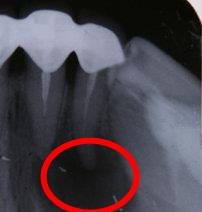

慢性根尖周炎造成的牙根膿包

拍片的膿包是這樣